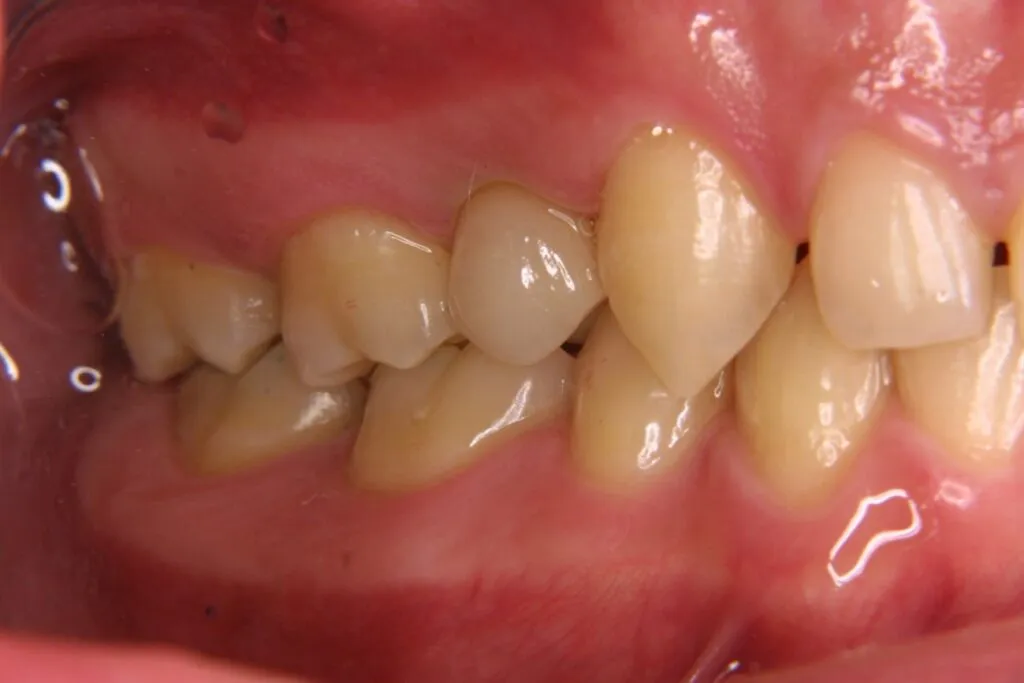

症例⑦

| 主訴 | 残根状態 歯を入れたい |

|---|---|

| 診断名 | 咀嚼障害 |

| 年齢 | 29歳 |

治療に用いた装置(治療法) | インプラント |

| 部位 | 左上6・左上7・左下6・左下7 |

| 治療期間 | 8か月 |

| 治療費用 | 1,848,000円 |

| リスク・副作用(治療に関する) | 腫脹、しびれ |